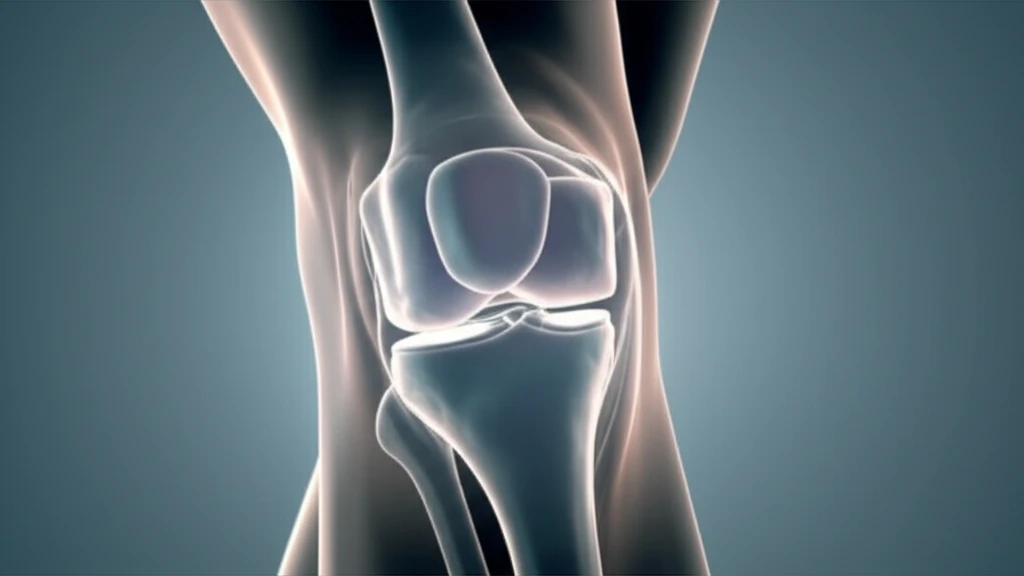

Anterior Cruciate Ligament (ACL) injuries are a common setback, especially for athletes. Traditional ACL reconstruction uses either autografts (tissue from your own body) or allografts (tissue from a donor) to repair the torn ligament. While effective, the recovery process can be lengthy, and athletes are eager to return to their pre-injury activity levels as quickly as possible.

A 23-year-old female skier with an MRI-confirmed ACL tear underwent arthroscopic-assisted ACL reconstruction. In this procedure, a quadruple-stranded hamstring autograft (tissue taken from the patient's hamstring tendons) was augmented with a dHACM allograft patch (AmnioFix, MiMedx Group, Inc.).